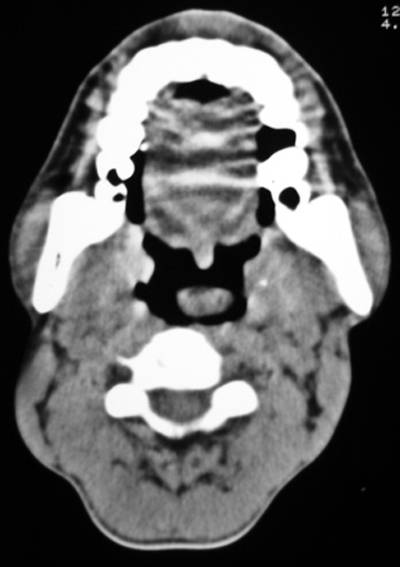

以下是引用syfszcw在2009-4-23 13:21:00的发言:[br]双侧上颌窦 筛窦慢性炎症,鼻息肉 会厌ca[br][br][本贴已被 syfszcw 于 2009-4-23 13:36:46 修改过]

以下是引用随光逐影在2009-4-23 19:35:00的发言:[br]1)鼻咽、口咽、左侧鼻腔及右侧鼻后孔处新生物,考虑息肉可能性大。2)双侧上颌窦及双侧筛窦炎症,不排除双侧上颌窦内息肉可能。